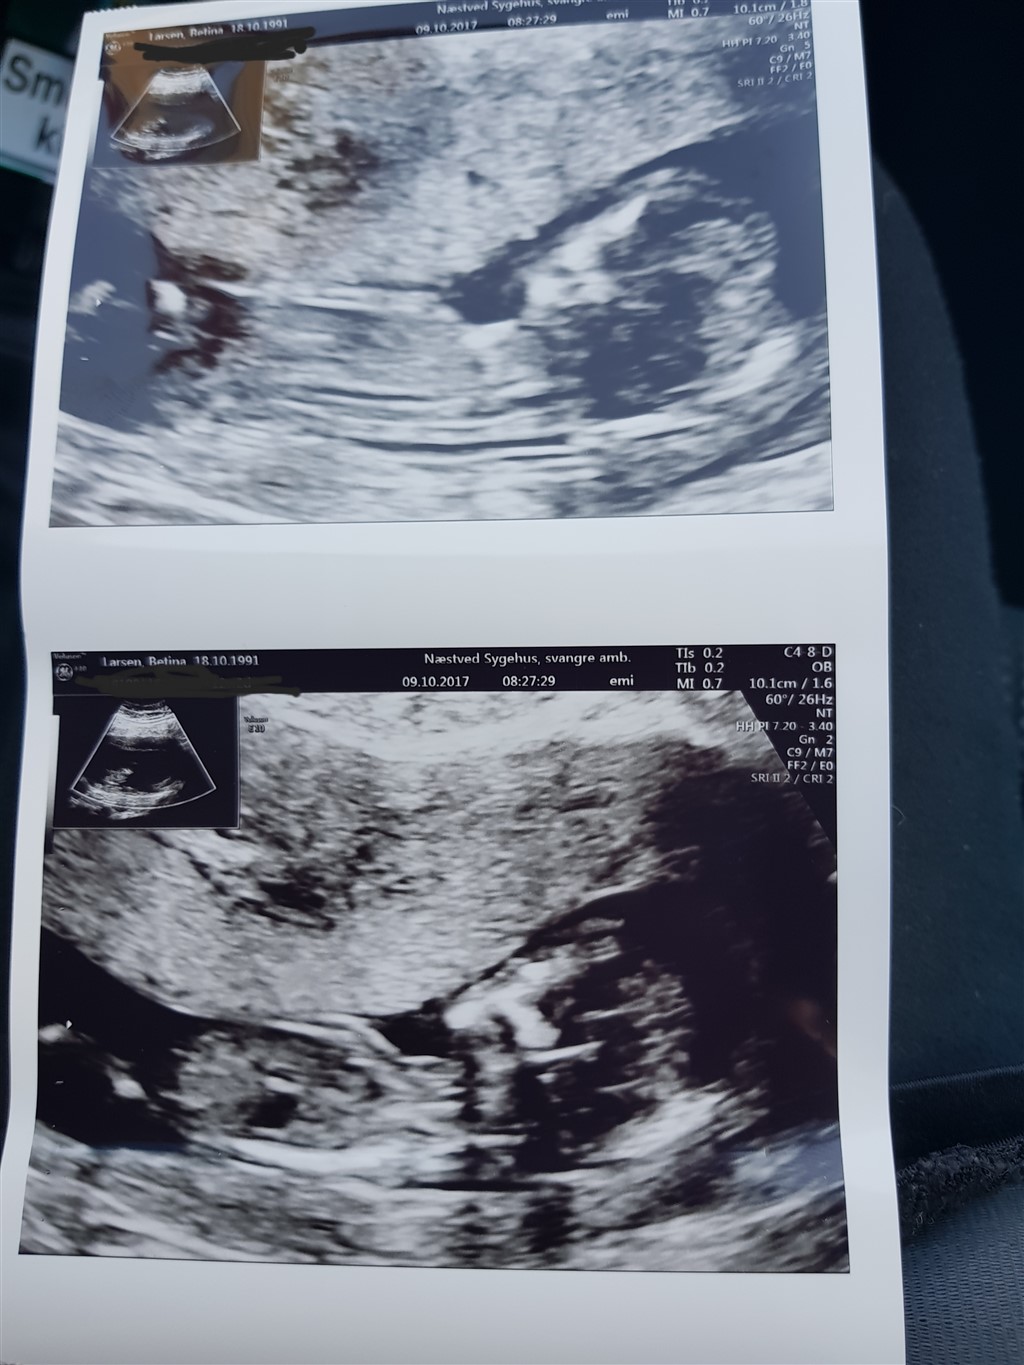

som overskriften lyder nogle der kender til den og kan i se en nub på billedet  og tør i at gætte ?? Jeg fatter det nemlig slet ikke  og kan ikke se den såkaldte nub

Det er ikke helt vildt tydelige billeder, men ud fra den smule der kan ses, vil jeg ud fra nub teorien gætte på pige, men ud fra skull teorien gætte på en dreng.

Nub teorien bygger på at hvis nub'en er parallel med rygraden så er det en pige, og peger den væk fra rygraden er det en dreng. Tidligt i graviditeten vil alle nub'er dog tyde på pige. Nub'en ses som en hvid "pind" der hvor der senere kommer kønsorganer.

Skull teori bygger på formen af fosterets kranie. Piger har et mere rundt kranie, hvor drenges er mere firkantede i det...

Hvis nubben er parallel med rygsøjlen eller max 30 grader derfra siger man pige. Hvis sen peger mere opad så siger man dreng. Og jeg synes den ser meget parallel ud på dine billeder